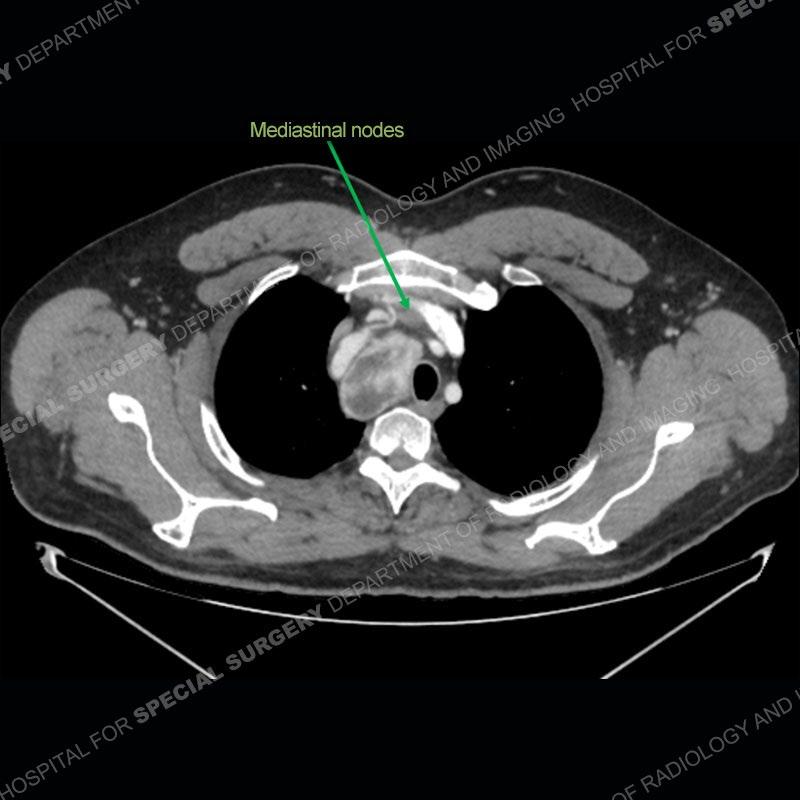

Findings

The chest radiographs demonstrate a leftward deviation of the trachea. CT images demonstrate a large, somewhat heterogeneous mass of the thyroid that extends outside the confines of the thyroid tissue. There is a subtle, enhancing soft tissue mass of the proximal right humerus. Slightly prominent mediastinal lymph nodes are present with additionally, multiple supraclavicular lymph nodes.

Although not strictly a part of the evaluation of an “incidental” thyroid lesion, evaluation of the adjacent lymph nodes and bony structures can also be quite important. In this case, there is an enhancing mass of the right humerus. This is very subtle and can only really be recognized by evaluating the density of the bone. Typicaly marrow will have a fatty density or nearly fluid density. As the density, as in this case, approaches soft tissue an infiltrative process must be entertained. Thyroid mets are markedly vascular accounting for the areas of enhancement of the humeral mass. The mediastinal and supraclavicular lymph nodes although not individually enlarged, should raise suspicion of an underlying inflammatory/neoplastic process.